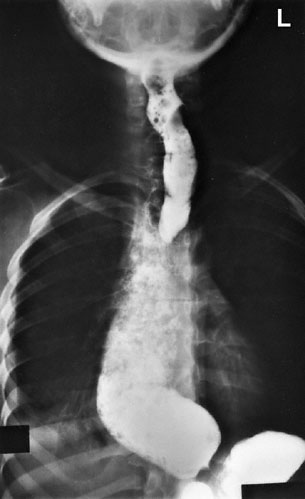

A previously healthy 47-year-old man comes to the physician because of progressive difficulty swallowing during the past 3 months. He reports that both solid foods and liquids seem to “get hung up” behind the lower part of his breast bone. He has had to take smaller bites, chew better, and eat more slowly than he has in the past. He has not had any change in weight. Physical examination shows no abnormalities. A barium swallow is shown. Which of the following is the most likely cause of this patient’s symptoms?